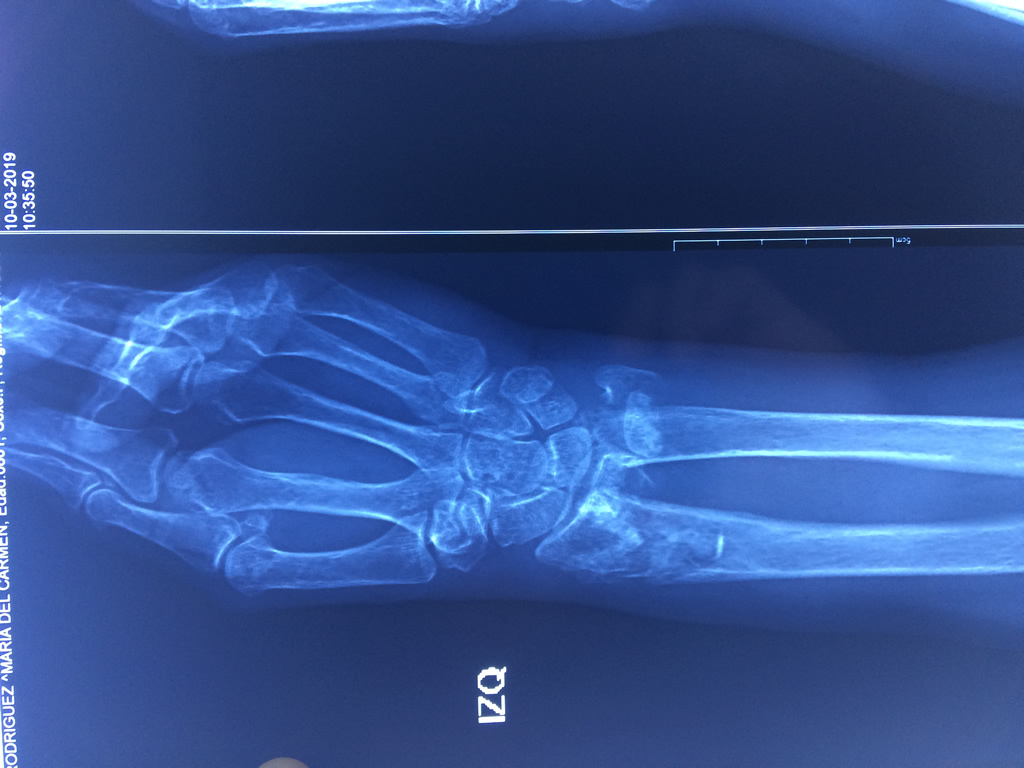

Cirugías de Húmero - Cirugías de Muñecas y Manos

Los procedimientos más comunes en cirugía de la mano son aquellos destinados a reparar traumatismos, incluyendo lesiones de tendones, nervios, vasos sanguíneos, y articulaciones; huesos fracturados; y quemaduras, cortes, y otros daños de la piel.